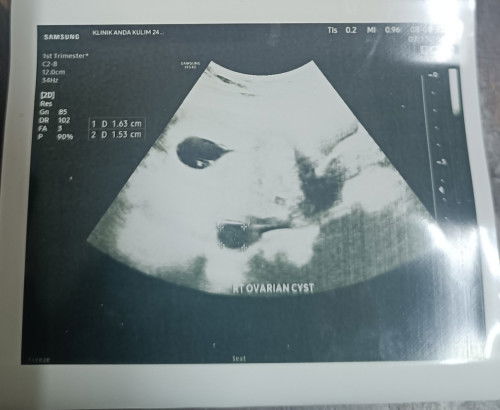

Cyst ketika mengandung

Cyst akan ganggu tak semasa mengandung ni sebab anak 1st tak pernah ada cyst..perlu ka risau? ##bantujawab #pregnancy #Needadvice

cyst akan mengecil sebab baby membesar dalam rahim..tapi cyst x akan hilang..x pasti sebab sy 1st & 2nd cyst masih ada..cyst nak buang rasa kena minor operate kot

saya anak first xde cyst . ni preg baby no 2 tiba ada pulak tapi xbesar sgt . next week jumpa doc pakar tgk cam mana . makin besar atau kecik .